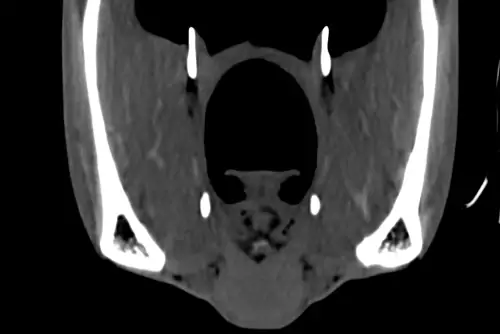

Same horse, same day ... so what have we done to make the CT scan on the left (image 1) look different from the middle one (image 2)?

We have injected contrast into the veins which we can see highlighting the blood vessels (white arrow heads) and the pituitary gland (black arrow) at the base of the brain (image 3).

Contrast enhanced CT is useful for assessing regions of increased or decreased blood flow or leaking blood vessels. This helps us identify soft tissue lesions and infectious or inflammatory processes. The use of contrast enhanced CT imaging is a huge asset to us at BELL EQUINE to improve diagnosis using our state-of-the-art CT scanner and can be performed in standing horses.

(Image 1: pre-contrast; image 2: post contrast; image 3: marked up image showing contrast uptake)